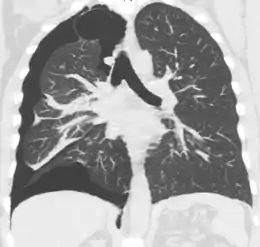

CT with the identification of underlying lung lesion: an apical bulla on the right side

A CT scan is not necessary for the diagnosis of pneumothorax, but it can be useful in particular situations. In some lung diseases, especially emphysema, it is possible for abnormal lung areas such as bullae (large air-filled sacs) to have the same appearance as a pneumothorax on chest X-ray, and it may not be safe to apply any treatment before the distinction is made and before the exact location and size of the pneumothorax is determined.[15] In trauma, where it may not be possible to perform an upright film, chest radiography may miss up to a third of pneumothoraces, while CT remains very sensitive.[18]

A further use of CT is in the identification of underlying lung lesions. In presumed primary pneumothorax, it may help to identify blebs or cystic lesions (in anticipation of treatment, see below), and in secondary pneumothorax, it can help to identify most of the causes listed above.[15][19]